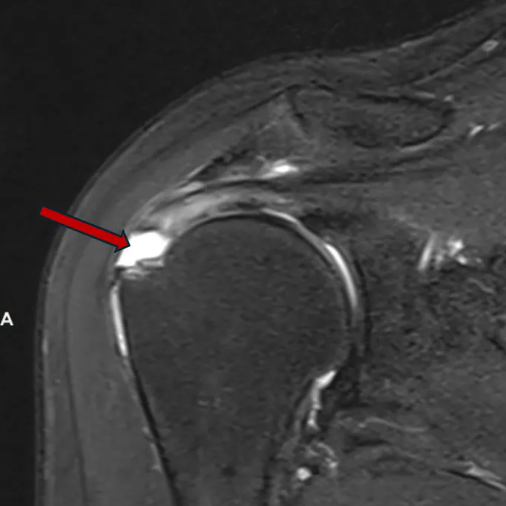

冈上肌腱完全撕裂,肌腱挛缩(白色,深红色箭头所示)